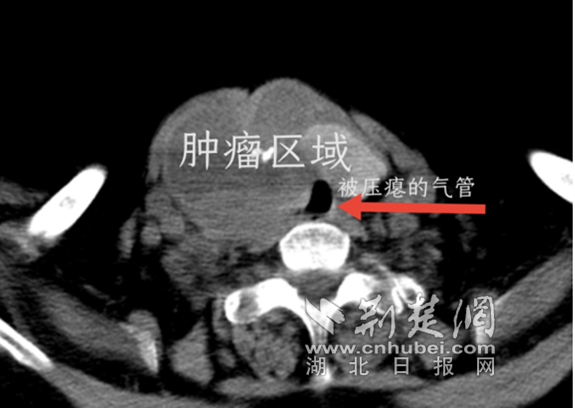

为解除颈部压迫,阮剑主任第一时间为王婆婆手术。术中发现肿瘤已经侵犯到周围的神经、血管、气管等组织,肿瘤像几块坚硬的石头一样将气管压成了"一线天",王婆婆随时可能因为窒息导致死亡。经过手术团队的努力,王婆婆颈部的"大石头"被搬走,气管压迫解除。术后王婆婆再也没有做过被人掐脖子的噩梦。

肿瘤将气管压成了"一线天" 通讯员 供图